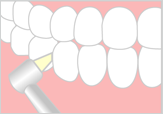

3.研磨

染出しの結果を基に、汚れの付いている着色部分を徹底的にきれいにしてきます。

歯と歯の隣接面の汚れをプラスチックのチップでこすり落とします。

歯と歯の隣接面の汚れをプラスチックのチップでこすり落とします。

歯と歯肉縁下の汚れをラテックスゴムのカップやブラシで落とします。

歯と歯肉縁下の汚れをラテックスゴムのカップやブラシで落とします。